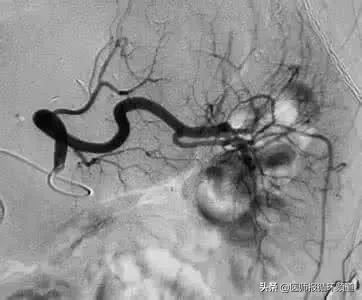

图3△